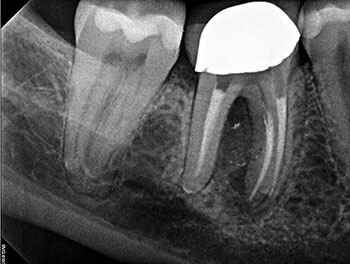

Case 1:A J-shaped lesion

Tooth #30 had a diagnosis of previous root canal treatment with symptomatic apical periodontitis. The mesial root had a classic J-shaped radiographic lesion and a narrow probing defect from the buccal furcation to the root apex. No crack could be seen on what little root surface was visible. The likelihood of VRF, or the possibility of a failing root canal with a chronic apical abscess, were discussed. The latter could be treatable. The plan was to attempt re-treatment after internal inspection for a possible VRF.

Fig. 1: Preoperative PA.

Fig. 2: Postoperative PA.